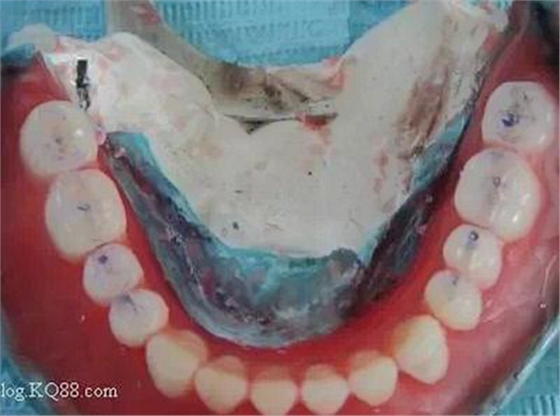

制取的下頜終印模。

四、灌制模型時(shí)盡量用硬石膏,這樣的石膏模型膨脹系數(shù)小,能保證義齒的準(zhǔn)確性和強(qiáng)度。在灌制模型時(shí),要注意把石膏灌制在印模邊緣外側(cè)少許,以在石膏模型上記錄下黏膜反折區(qū)。

患者原有的上頜義齒也可作為個(gè)別托盤(pán)使用。

記錄下的黏膜反折區(qū)。

在制作蠟型時(shí)要有效的利用這一區(qū)域,才能取得良好的邊緣封閉作用。